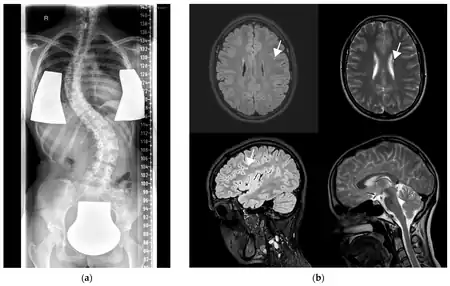

a) X-ray showing scoliosis b) MRI with left frontal FLAIR hyperintensity